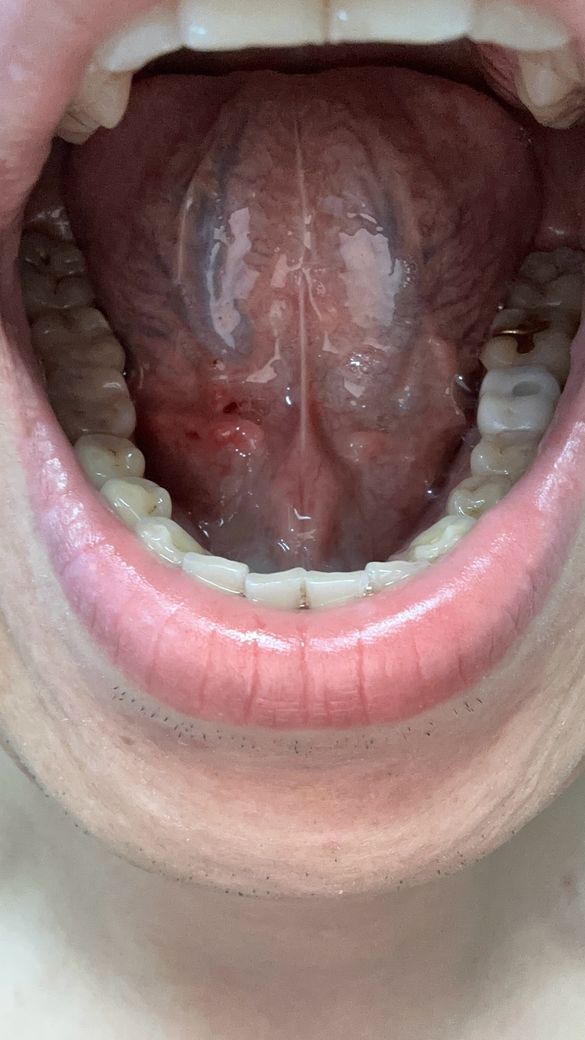

양치하다가 칫솔로 눌렀는데 아파지고 빨개진거같아요

빨갛게 된부분이 있는것같고 그래서 이거 병원가봐야되는지 그냥 냅둬도 괜찮음지 궁금해요 어떻게하는게 좋을까요?? 병원은 무슨과인가요?

• 1번 째 사진